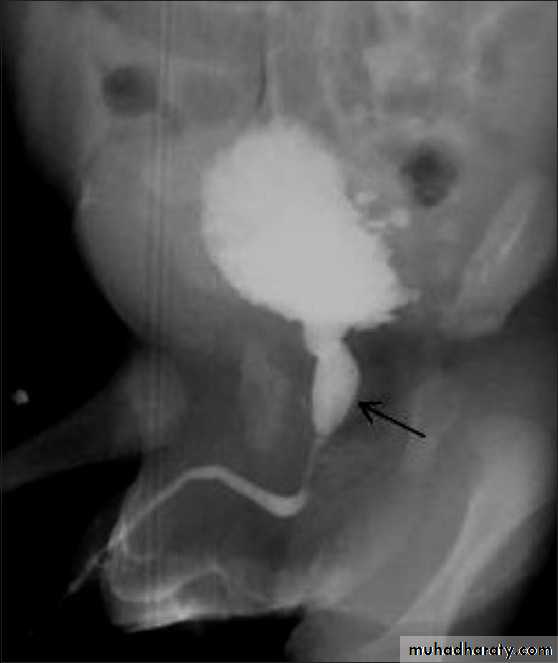

male &female reproductive tractsmammogram

genital tract and mammogram